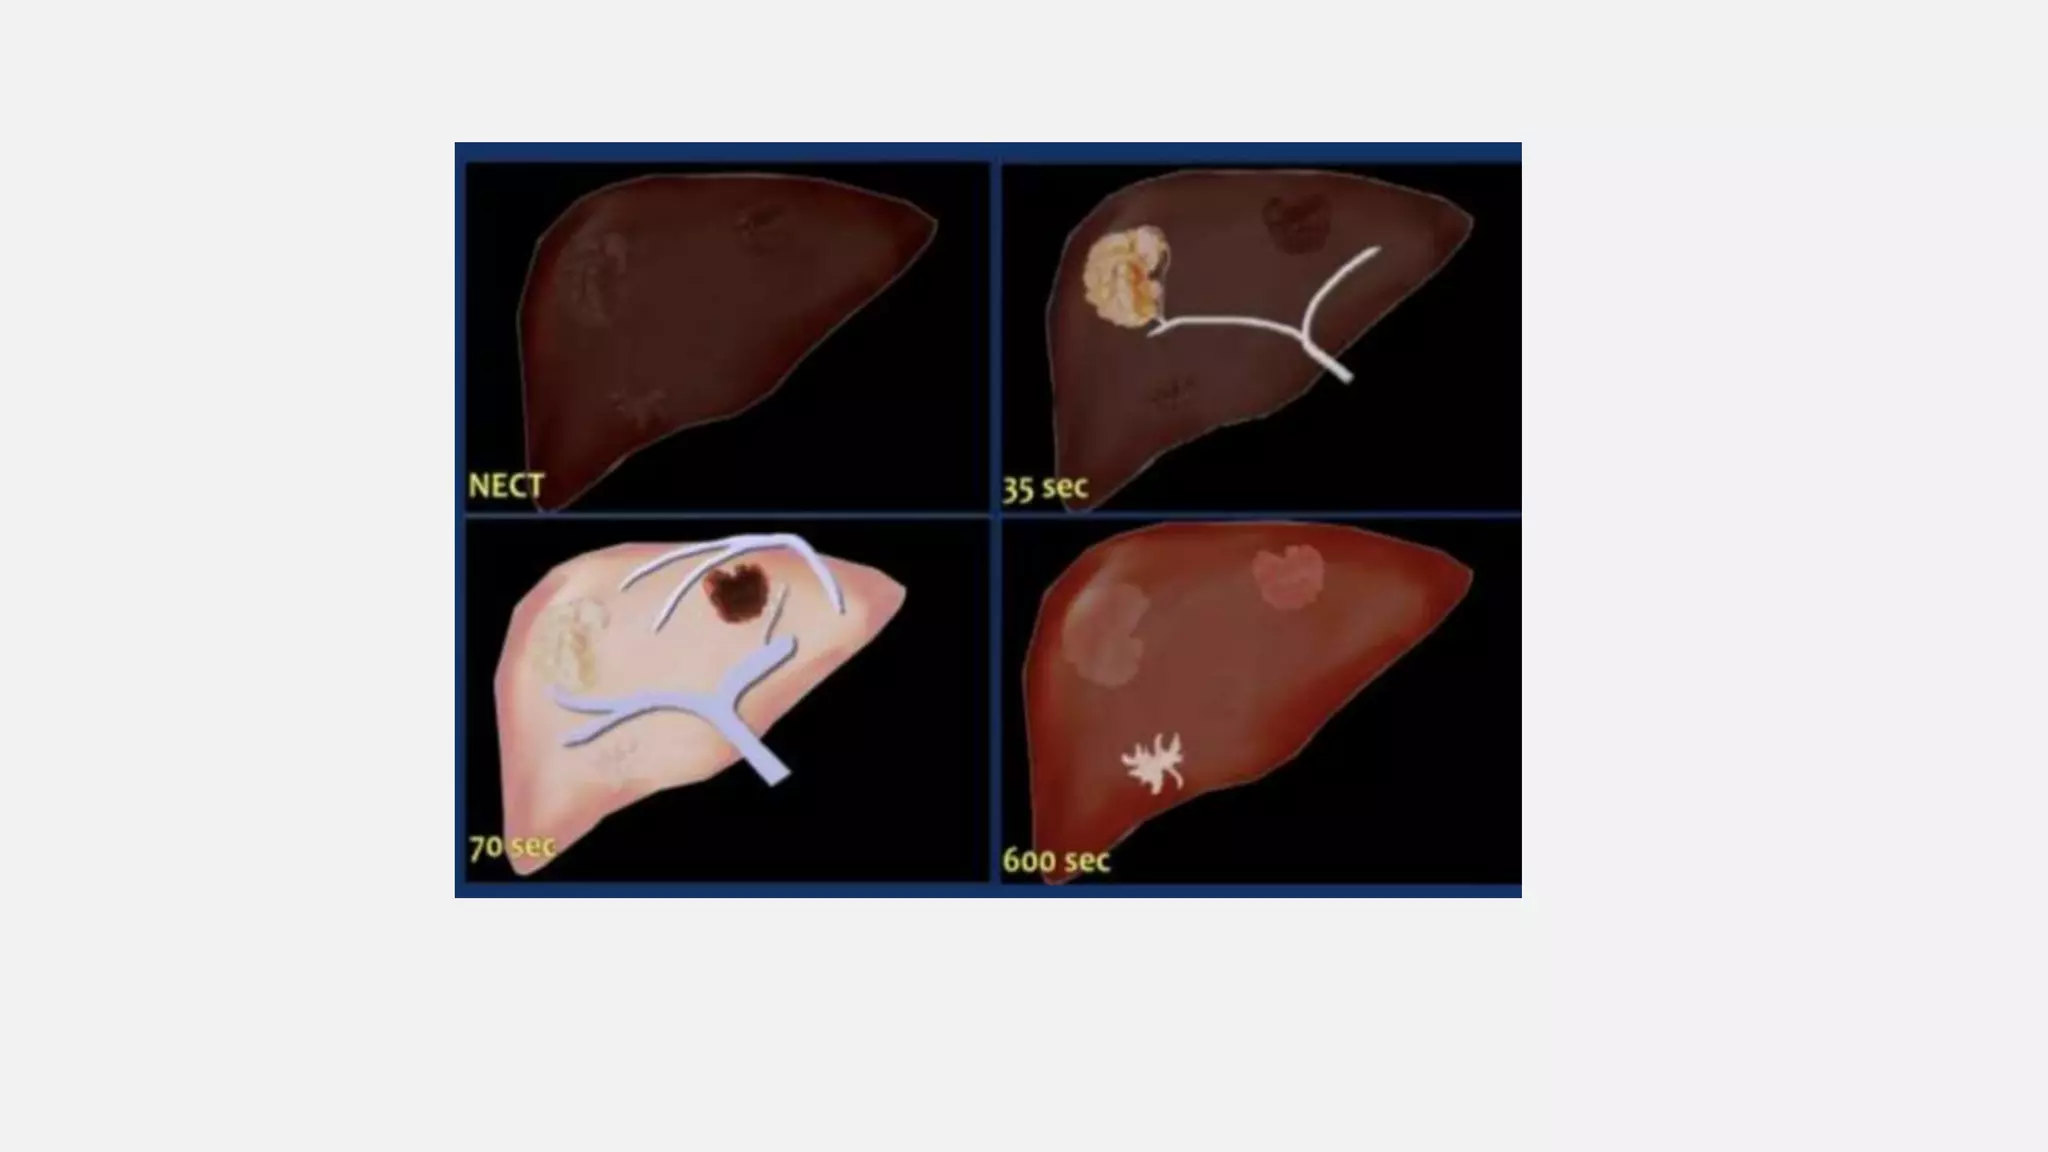

LIVER • All livertumours however get 100% of their blood supply from the hepatic artery. So a hyper vascular tumor will be best seen in the late arterial phase. • A hypo-vascular liver tumor however will enhance poorly in the late arterial phase, because it is hypo- vascular and the surrounding liver does also enhance poorly in that phase. This tumor is best seen when the surrounding tissue enhances, i.e. in the late portal (or hepatic) phase at 75-80 sec p.i. • The

• #37 The conspicuity of a liver lesion depends on the attenuation difference between the lesion and the normal liver. On a non enhanced CT-scan (NECT) liver tumors are not visible, because the inherent contrast between tumor tissue and the surrounding liver parenchyma is too low. When we give i.v. contrast, it is important to understand, that there is a dual blood supply to the liver. Normal parenchyma is supplied for 80% by the portal vein and only for 20% by the hepatic artery, so the normal parenchyma will enhance maximally in the hepatic phase at 70-80 sec p.i. and only a little bit in the late arterial phase at 35-40 sec p.i..

• #38 In the late arterial phase at 35 sec hypervascular lesions like HCC, FNH, adenoma and hemangioma wil enhance optimally, while the normal parenchyma shows only minimal enhancement. Hypovascular lesions like metastases, cysts and abscesses will not enhance and are best seen in the hepatic phase at 70 sec p.i. Fibrotic lesions like cholangiocarcinoma and fibrotic metastases hold the contrast much longer than normal parenchyma. They are best seen in the delayed phase at 600 sec p.i. This late enhancement is comparable to what is seen in cardiac infarcts in MRI of the heart.